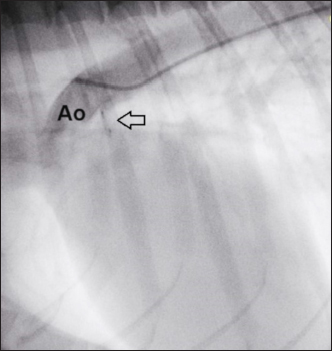

A 3.3-French MP angiographic catheter (Moongoose® Togo Medikit Co. Ltd., Oaza Hichiya Hyuga City, Japan) was placed into the femoral artery together with a 0.025” angled hydrophilic guidewire, 180-cm long (Terumo Radiofocus® Glidewire, Terumo Medical Corporation), through the 4-French vascular sheath. Once it had reached the ascending aorta, it was used to perform angiography (after removing the guide wire) with 3 mL iodinated contrast agent (350 mg/mL) diluted with 3 mL saline, to facilitate its manual injection through the 3.3-French vascular catheter. Angiography confirmed the earlier measurements of TEE.

Fig. 6. Angiography conducted after device (arrow) release. The PDA is completely occluded and no residual shunt is visible.